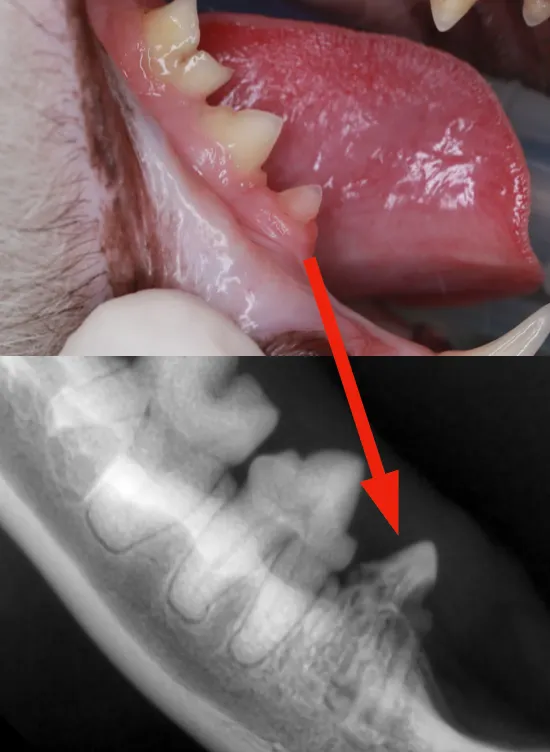

또한 치아를 유심히 관찰해 보면

아래 사진처럼

치아 위쪽으로 잇몸이

빨갛게 올라오는 것이

관찰됩니다.

위의 사진처럼 육안검사상

큰 문제가 없어 보이는

치아의 경우에도

치아 방사선 검사상

치아 흡수성 병변이

보이는 것을 알 수 있습니다.